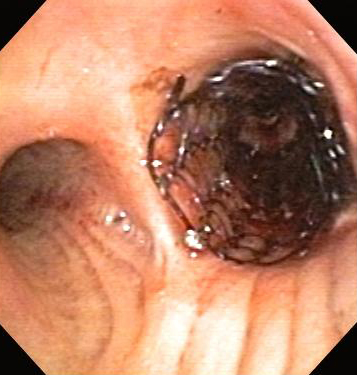

In general, endoscopic management involves less risk, discomfort, and morbidity than surgical treatment.[Figure caption and citation for the preceding image starts]: Post-lung transplant anastomotic bronchial stenosisFrom the collections of Jose Fernando Santacruz MD, FCCP, DAABIP and Erik Folch MD, MSc; used with permission [Citation ends].

[Figure caption and citation for the preceding image starts]: Post-lung transplant anastomotic bronchial stenosis: right mainstem anastomosis post-multimodal endoscopic therapyFrom the collections of Jose Fernando Santacruz MD, FCCP, DAABIP and Erik Folch MD, MSc; used with permission [Citation ends].